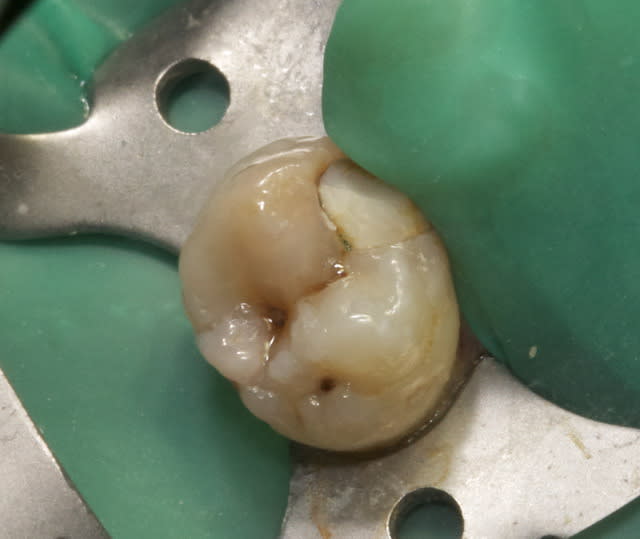

46 - fig 1,2 situation initiale

Fase du traitement: seule visite 2h

- percussion - positive

- teste du vitalité - négative

NaOCl 5% - l'irrigation et l'activation par ultrasons

chaud condensation de gutta-percha

build-up